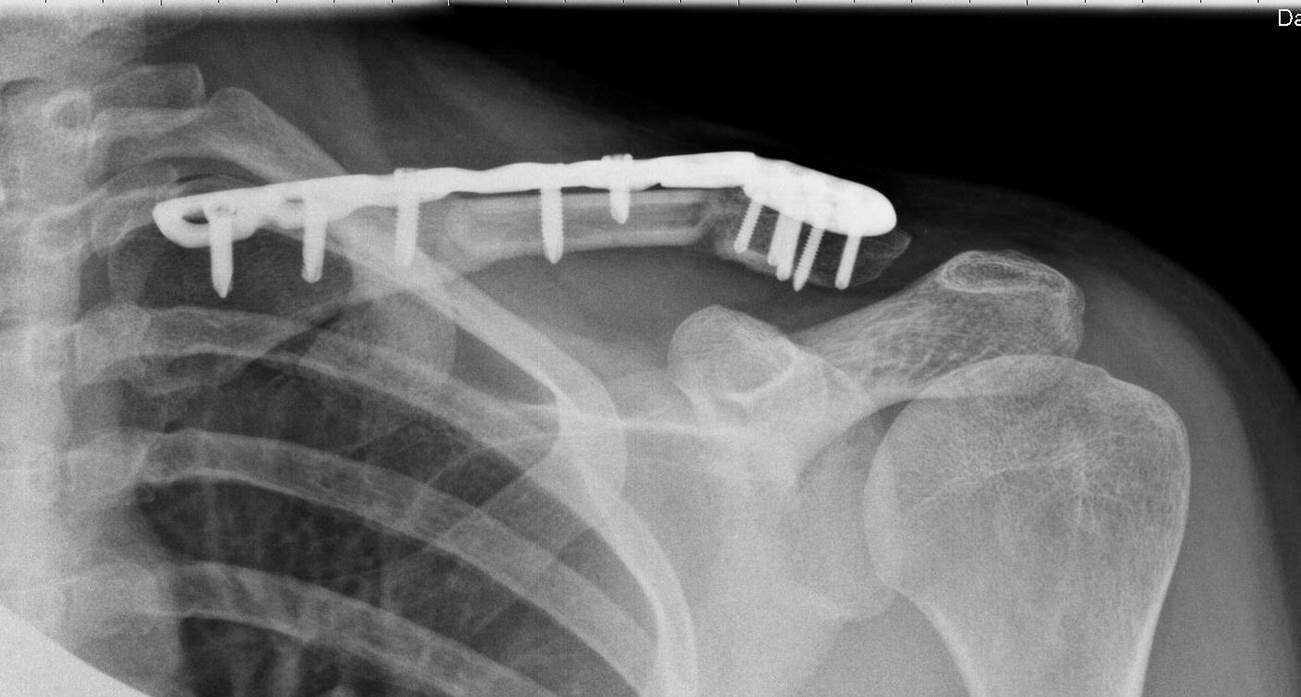

Рис.2. Пациентка, 31 год. 3 месяца после операции. Срастающаяся левая ключица после разрушения ложного сустава, костной пластики свободным кровоснабжаемым аутотрансплантатом, фиксации костных отломков пластиной и винтами. Рис.3. Пациентка, 31 год. 12 месяцев после операции. Срастающаяся левая ключица после разрушения ложного сустава, костной пластики свободным кровоснабжаемым аутотрансплантатом, фиксации костных отломков пластиной и винтами